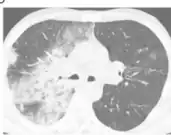

Diagnosis

.png)

The diagnosis of bacterial pneumonia is based on the following:[5]

- Chest X-ray